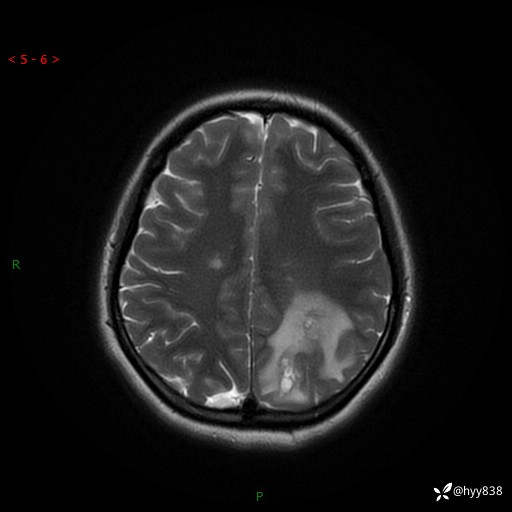

颅脑MRI平扫+增强